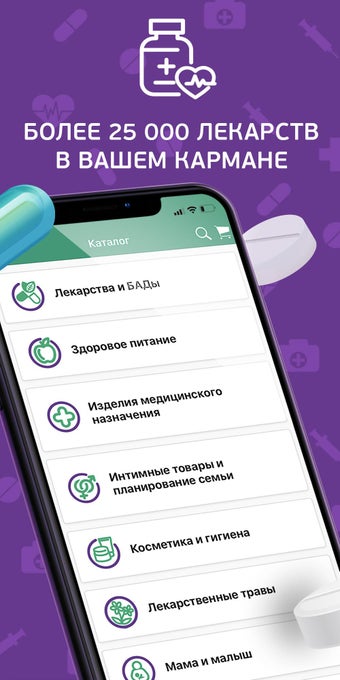

Ứng dụng cung cấp đầy đủ hướng dẫn cho mỗi loại thuốc. Bạn có thể chọn một loại thuốc dựa trên chất hoạt động của nó, hoặc sử dụng nó cho các triệu chứng. Ví dụ, nếu bạn cần một loại thuốc để điều trị huyết áp cao của mình, bạn có thể chọn một loại thuốc để điều trị tăng huyết áp. Hoặc nếu bạn bị nhiễm trùng dạ dày, bạn có thể chọn một loại thuốc để điều trị viêm dạ dày.

Bạn có thể sử dụng ứng dụng để tìm kiếm các loại thuốc không có sẵn trong nhà thuốc của bạn, đặt hàng giao hàng đến nhà của bạn hoặc đặt hàng từ một nhà thuốc gần bạn.

Bạn có thể sử dụng ứng dụng để tìm kiếm bất kỳ loại thuốc nào, bất kể nó có sẵn trong nhà thuốc địa phương của bạn hay không.